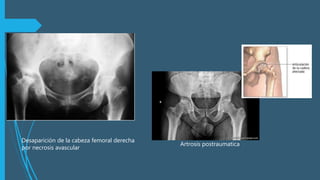

• Osteonecrosis (5-40%)sobre todo en

reducciones después de las primeras 6 hrs,

aparece varios años después.

• Artrosis postraumática es la + frec.,su

incidencia es alta asociada a fx de acetábulo

o fx transcenderles de fémur.

Artrosis postraumatica

Desaparición de la cabeza femoral derecha

por necrosis avascular

Complicaciones  Las complicacionespueden ser tempranas o tardías, dependiendo del momento de su presentación. Tempranas Tardías • Lesión del nervio ciático (10- 15%)en lux. Post. • Lesión vascular en lux. ant • Luxación irreductible (5%- 15%) • Osteonecrosis (5-40%)sobre todo en reducciones después de las primeras 6 hrs, aparece varios años después. • Artrosis postraumática es la + frec.,su incidencia es alta asociada a fx de acetábulo o fx transcenderles de fémur. • Miosotis osificarte < 2% • Luxación recurrente es rara < 2%

Artrosis postraumatica Desaparición dela cabeza femoral derecha por necrosis avascular